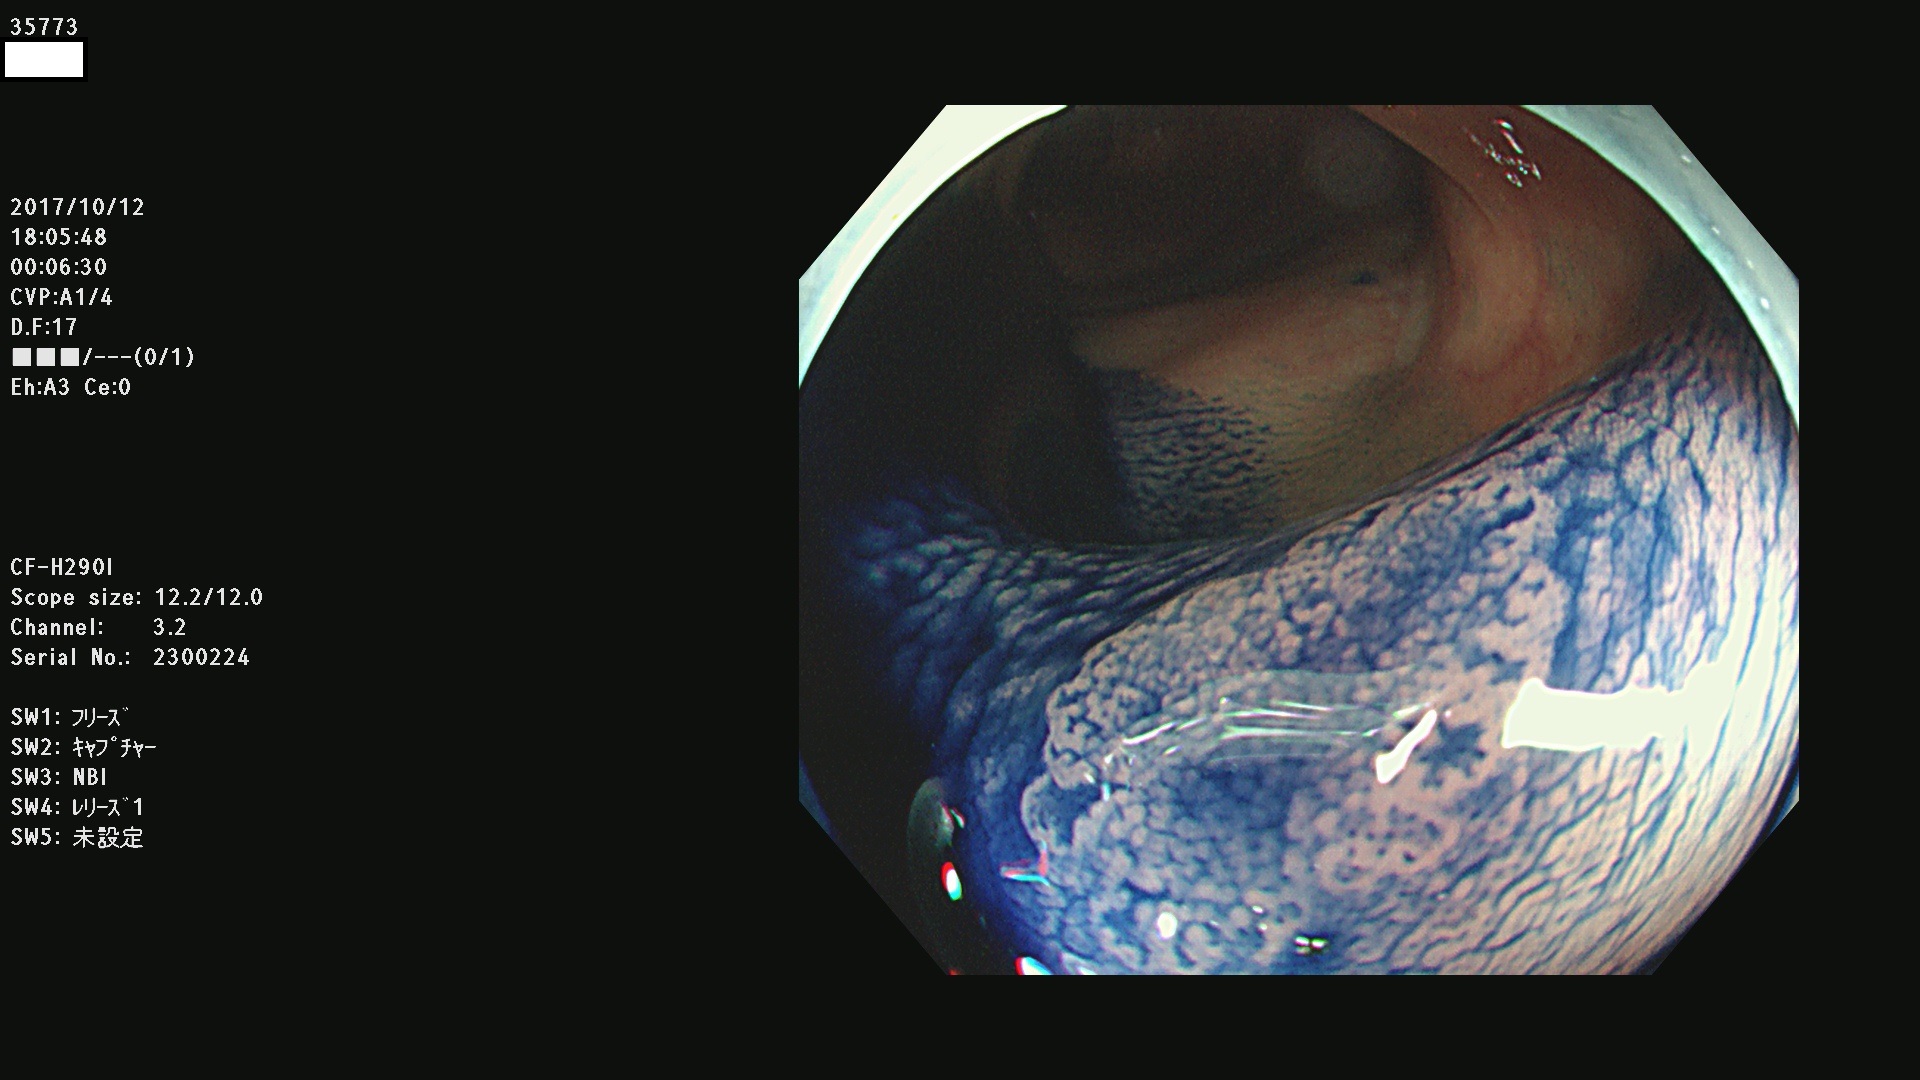

35700 35701 35704 35706 35707 35708 35709 35711(SSA/Pのみ) 35715 35716 35717 35718 35720(SSA/Pのみ) 35722 3576(SSA/Pのみ) 35730 35732 35734(SSA/Pのみ) 35736(SSA/Pのみ) 35741 35742 35743 35744 35746 35748 35749(SSA/Pのみ)35755 35757 35760 35761 35762 35763 35764 35766 35767 35770 35772(SSA/Pのみ) 35773 35781 35783 35785 35786 35787 35788 35791 35795 35796 35797 35798 35799

発見困難で危険性の高い平坦型病変(上記100名より抽出)